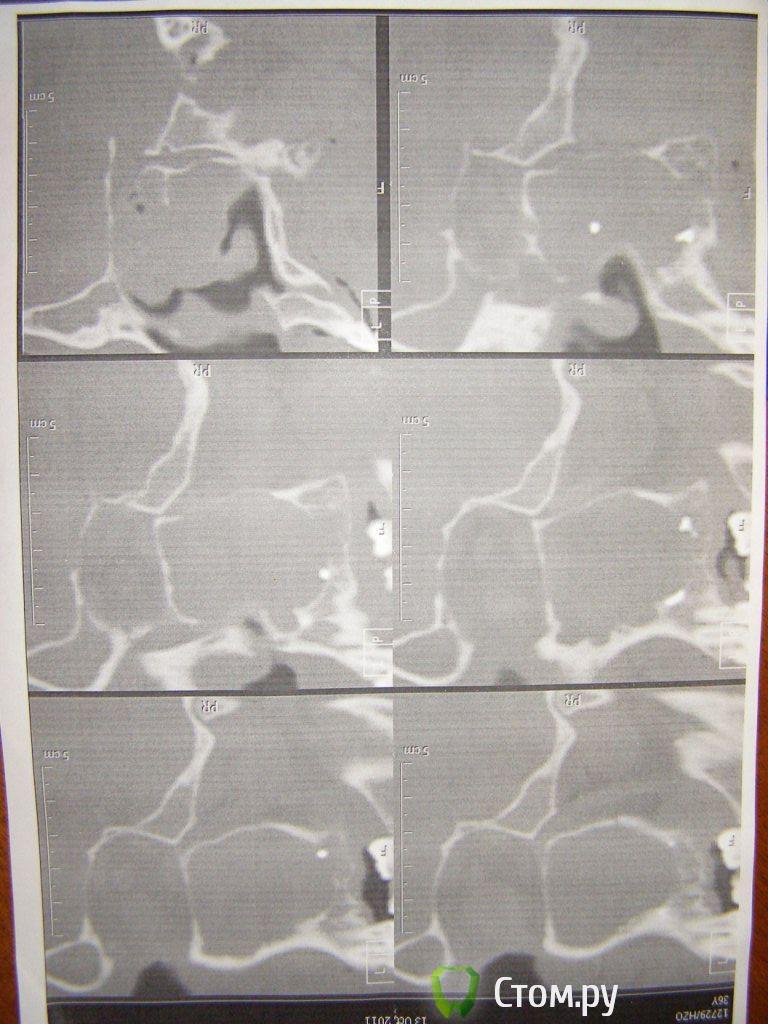

Евений Опубликовано 15 ноября, 2011 Поделиться Опубликовано 15 ноября, 2011 (изменено) Здравствуйте!Мужчина, 36 лет.Расскажу, что беспокоит.Летом, в июле начала *немного болеть разрушенная верхняя шестерка, зуб мертвый и коронковая часть почти вся сколота, корешок был коричнево-черного цвета. Вокруг оставшейся части зуба опухла десна и ее было больно нажимать. Проходил так все лето, когда начинал беспокоить зуб, делал полоскания содой и фурацилином. В таком состоянии доходил до осени. Вспомнил, что еще в августе немного закладывало нос, но почти незаметно. Однажды проснулся и был неприятно удивлен полностью заложенной ноздрей, понял, что если это произошло на стороне плохого зуба, то есть какая-то связь. на следующий день побежал рвать шестерку. После удаления ничего не изменилось. Сейчас беспокоит заложенность одной ноздри, если начинаю пить синупрет, наблюдаю откладывание и выход большого количества прозрачно-желтой слизи без запаха. Никакой болей и тяжести нет. Сделал томографию месяц назад-Вот результат исследования:тотально заполнена содержимым правая лобная, правая верхнечелюстная пазухи, ячейки решетчатой кости справа.Основная и левая пазухи пневматизированы.На фоне масс заполняющих правую верхнечелюстную пазуху визуализируется овоидное, более плотное образование 1,6 Х 1,3 см, в центре которого металлической плотности объект. Медиальная стенка правой верхнечелюст пазухи не определяется (разрушена?), мягкотканные массы из пазухи пролабируют в верхний и средний носовой проход.Нижняя стенка верхнечел пазухи нечеткая, здесь расположены несколько мелких объектов металлической плотности. Заключение- более вероятным представляется наличие выраженного риносинусита на фоне наличия в правочелюст пазухе пломбировочного материала. Вопрос к вам, уважаемые специалисты - я так понял в пазухе куча инородных тел. На ортопантограмме аж 3 штуки, и еще в середине где-то, которое видно на КТ. Вопрос такой- каким образом это все убрать? Возможно ли это сделать через лунку удаленного зуба или нужно произвести микрогайморотомию? Пожалуйста, посмотрите КТ и ортопантограмму(качество ужасное, конечно, извините) Заранее огромное спасибо за помощь! Изменено 15 ноября, 2011 пользователем Евений Ссылка на комментарий

Евений Опубликовано 15 ноября, 2011 Автор Поделиться Опубликовано 15 ноября, 2011 вот фото КТ и ортопантограммы Ссылка на комментарий